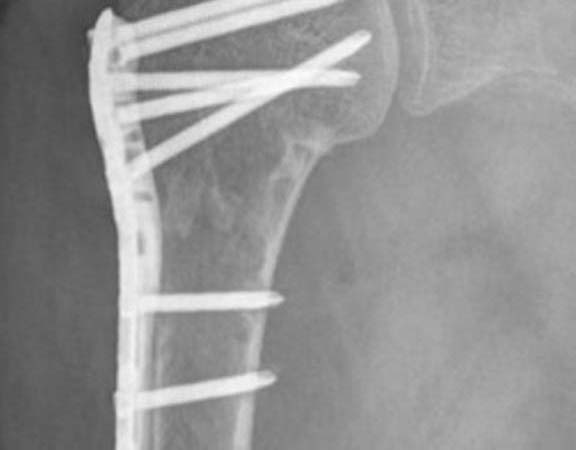

FRATURAS DO OMBRO

As fraturas do úmero proximal acontecem basicamente em 2 perfis de paciente: em jovens após acidente de alta energia, principalmente queda de moto, e outra, no paciente acima de 50 anos, que simplesmente caem, frequentemente relacionada ao osso com osteoporose. Dor no ombro, impossibilidade de mexer e hematoma. Este último pode se espalhar pelo peito e braço Após a avaliação médica, no serviço de emergência, exame de raio-X será solicitado. Algumas vezes a tomografia computadorizada esclarece detalhes quando a fratura é complexa. Ressonância magnética é solicitada nos casos em que a suspeita de fratura é grande, porém o exame radiológico é normal. São os casos de fraturas ocultas. O tratamento para a maior parte dessas fraturas é com tipóia. Repouso do membro acometido por aproximadamente 45 dias é suficiente para a consolidação do osso. A cirurgia é realizada para aqueles pacientes que apresentam grande desalinhamento dos fragmentos da fratura, fraturas dentro da articulação e fraturas com luxações. O principal meio de fixação é com placa e parafusos. Algumas vezes, dependendo do tipo de fratura e idade do paciente, é necessário substituir a região fraturada por uma prótese.